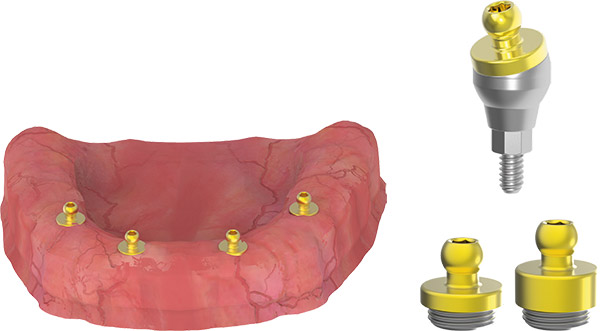

MULTI UNIT

LOCATOR ABUTMENT

CLOSED TRAY IMPRESSION TECHNIQUE

- Use the straight and/or 17-degree Multi Base Locator Abutment in the anterior region.

- Use the 30-degree Multi Base Locator Abutment in the posterior region.

- Mount the plastic pick up transfers used for impression on 17-30 degree Multi Base Locator Abutments.

- Take the impression.

Note: The recommended insertion torque when screwing the abutment is 25 Ncm.

LABORATORY PROCESSES

- Mount the analogs carefully on impression pick up pieces.

- Prepare the impression for transfer.

- Cast high quality plaster for the master model.

- The model is restored in the dental laboratory.

- Place the abutment on top.